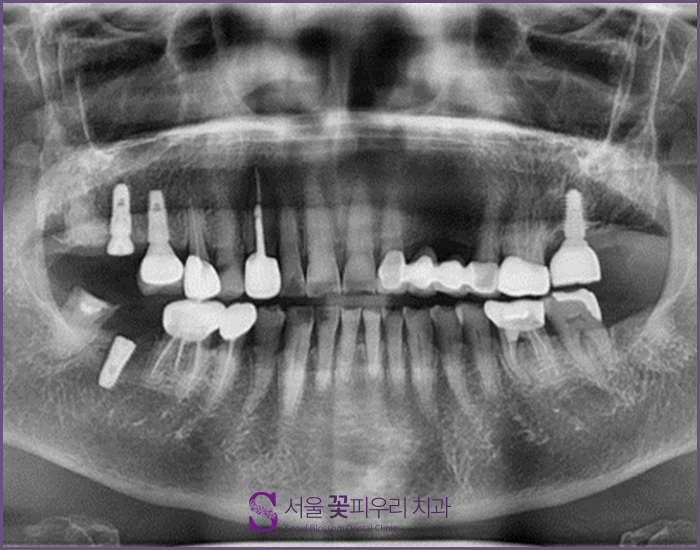

혈압약을 복용하고 계신 80대 노인분들의 사례= 대구 임플란트 치과에 오신 80대 여성 환자분께서 파노라마 X선 사진입니다. 그동안 잘 관리해주셔서 치아와 잇몸, 잇몸뼈의 상태가 아주 좋았는데 사진상으로 왼쪽으로 보이는 곳에 위아래 어금니에 임플란트를 해드리고자 하여 서울화 개화 우리치과를 찾아오게 되었습니다. 사전에 상담하면서 특이사항을 발견했는데, 이 환자가 심장 시술을 받은 경험이 있다고 합니다. 그래서 혈압약과 혈관확장제를 복용하고 있었는데, 이 약물들은 임플란트 시 절제한 부분에서 지혈을 어렵게 하는 약물들 때문에 환자가 다니던 내과와 협의하여 치료를 하게 되었습니다.

내과와 협의한 후 기존 약을 5일 정도 복용을 중단하고 임플란트 2개를 심기로 결정했습니다 이 사진은 환자분의 3DCT사진입니다. 상하 임플란트 매립을 희망하셨기 때문에 픽스처가 매입할 뼈의 길이와 골질이 충분히 확보되어 있는지 확인했습니다. 위턱은 문제가 없었지만 아래턱 부분에 골밀도가 부족했기 때문에 2회로 나누어 치료를 하게 되었습니다.